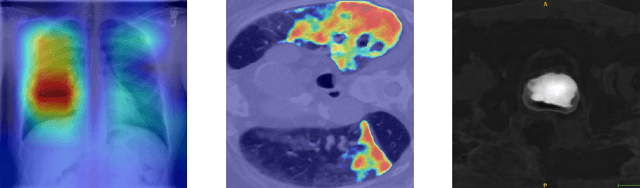

Abstract:Automatic segmentation of ground glass opacities and consolidations in chest computer tomography (CT) scans can potentially ease the burden of radiologists during times of high resource utilisation. However, deep learning models are not trusted in the clinical routine due to failing silently on out-of-distribution (OOD) data. We propose a lightweight OOD detection method that leverages the Mahalanobis distance in the feature space and seamlessly integrates into state-of-the-art segmentation pipelines. The simple approach can even augment pre-trained models with clinically relevant uncertainty quantification. We validate our method across four chest CT distribution shifts and two magnetic resonance imaging applications, namely segmentation of the hippocampus and the prostate. Our results show that the proposed method effectively detects far- and near-OOD samples across all explored scenarios.

Abstract:Automatic segmentation of lung lesions in computer tomography has the potential to ease the burden of clinicians during the Covid-19 pandemic. Yet predictive deep learning models are not trusted in the clinical routine due to failing silently in out-of-distribution (OOD) data. We propose a lightweight OOD detection method that exploits the Mahalanobis distance in the feature space. The proposed approach can be seamlessly integrated into state-of-the-art segmentation pipelines without requiring changes in model architecture or training procedure, and can therefore be used to assess the suitability of pre-trained models to new data. We validate our method with a patch-based nnU-Net architecture trained with a multi-institutional dataset and find that it effectively detects samples that the model segments incorrectly.

Abstract:M3d-CAM is an easy to use library for generating attention maps of CNN-based PyTorch models improving the interpretability of model predictions for humans. The attention maps can be generated with multiple methods like Guided Backpropagation, Grad-CAM, Guided Grad-CAM and Grad-CAM++. These attention maps visualize the regions in the input data that influenced the model prediction the most at a certain layer. Furthermore, M3d-CAM supports 2D and 3D data for the task of classification as well as for segmentation. A key feature is also that in most cases only a single line of code is required for generating attention maps for a model making M3d-CAM basically plug and play.